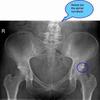

Pain in groin and front of thigh

So whenever I am squatting with weight or even sometimes simply squatting, I have a slight pain shoot from the top of my knee to mid thigh. It is very brief, but then that section goes tingly and somewhat numb for about an hour.

I noticed this about a year ago when squatting in the gym and noticed it again when lifting in crossfit class today. I had weight on a bar, and squatted with the weight and the tingles went from "eh" to painful, I am not sure what to do or where to go from here.

The question is: is this strained quad muscle, or is this a pinched femoral nerve, or one of the branches of the femoral nerve.